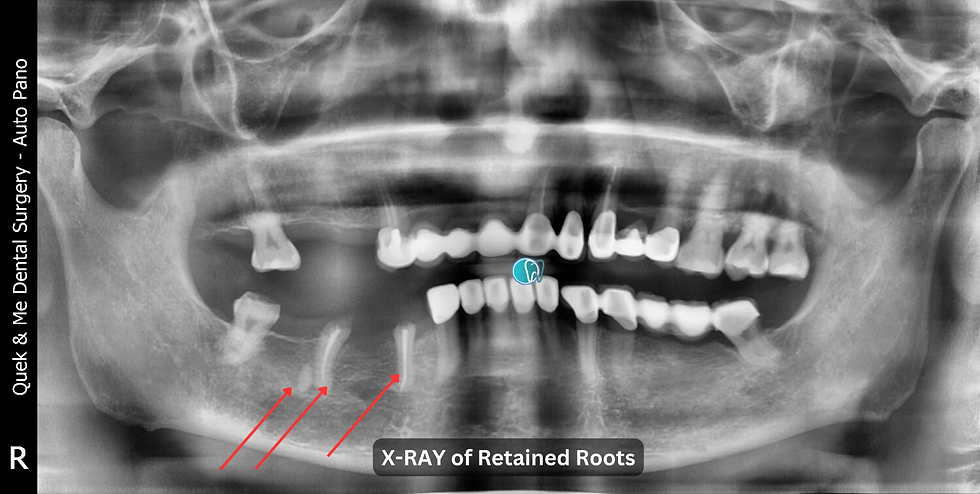

Surgical Removal of Retained Roots for #44, #45, #46

Teeth #44 & #45: Retained roots with gross subgingival caries

Tooth #46: Retained mesial root, buried and retained

Findings: Long, curved retained roots in teeth #44 & #45, prior root fillings (RF), normal periapical region

Retained mesial root of tooth #46 plotted near the inferior dental nerve (IDN)